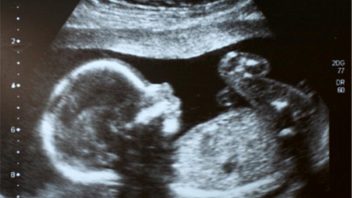

In vitro fertilizace (IVF) neboli oplodnění ve zkumavce již dávno není horkou novinkou. První takové dítě se u nás narodilo 4. listopadu 1982 na I. ženské klinice ve Fakultní nemocnici KÚNZ v Brně (čtyři roky po světové premiéře). Mimotělní oplodnění (IVF), také nazývané oplodnění ze zkumavky, lze použít u všech párů s výjimkou těch, které nemají předpoklady pro donošení plodu. Vše začíná stimulací vaječníků. Následuje odběr vajíček a posléze oplodnění vajíček a kultivace embryí.